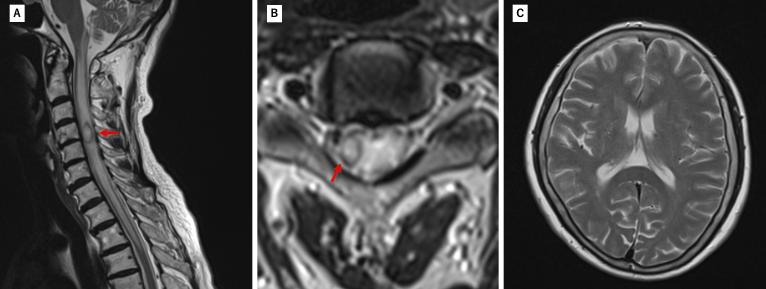

髓内脊髓脓肿很少引起意识受损而不引起颅内感染。我们报告的情况下,65岁的妇女谁提出颈部疼痛和右上肢无力。入院三天内,她的意识迅速恶化。最初的磁共振成像显示右侧C4-C5髓内病变,周围水肿延伸至脑干。脑成像未见异常。初步诊断为脊髓肿瘤。随访影像学显示病灶扩大伴环形强化。患者随后出现意识受损和四肢瘫痪。急诊手术发现并排出脊髓脓肿,培养物生长α-溶血性链球菌。手术后病人的意识恢复得很快。入院时发现先前未确诊的2型糖尿病。经广泛调查,未发现明显传染源。氨苄西林抗生素治疗持续1个月。两个月后的影像学显示脓肿完全消退。患者康复后恢复独立行走能力,仅残留轻微右臂无力。随访10年未见复发。本病例表明,颈脊髓脓肿可通过脑干水肿引起意识受损,而不发生颅内感染。早期手术干预配合适当的抗生素治疗可获得良好的结果。

Intramedullary spinal cord abscesses rarely cause impaired consciousness without intracranial infection. We report the case of a 65-year-old woman who presented with neck pain and right upper limb weakness. She developed rapidly progressive impaired consciousness within three days of admission. Initial magnetic resonance imaging revealed a right-sided intramedullary lesion at C4-C5 with surrounding edema extending to the brainstem. Brain imaging showed no abnormalities. An initial diagnosis of a spinal cord tumor was made. Follow-up imaging demonstrated lesion expansion with ring enhancement. The patient subsequently developed impaired consciousness and quadriplegia. Emergency surgery revealed and drained a spinal cord abscess, with cultures growing α-hemolytic Streptococcus. The patient's consciousness improved quickly after surgery. Previously undiagnosed type 2 diabetes was identified during admission. Despite extensive investigation, no obvious source of infection was found. Antibiotic therapy with ampicillin was continued for one month. Imaging at two months showed complete resolution of the abscess. The patient regained independent walking ability after rehabilitation, with only slight residual right arm weakness. No recurrence was observed during ten years of follow-up. This case demonstrates that a cervical spinal cord abscess can cause impaired consciousness through brainstem edema without intracranial infection. Early surgical intervention combined with appropriate antibiotics may lead to favorable outcomes.